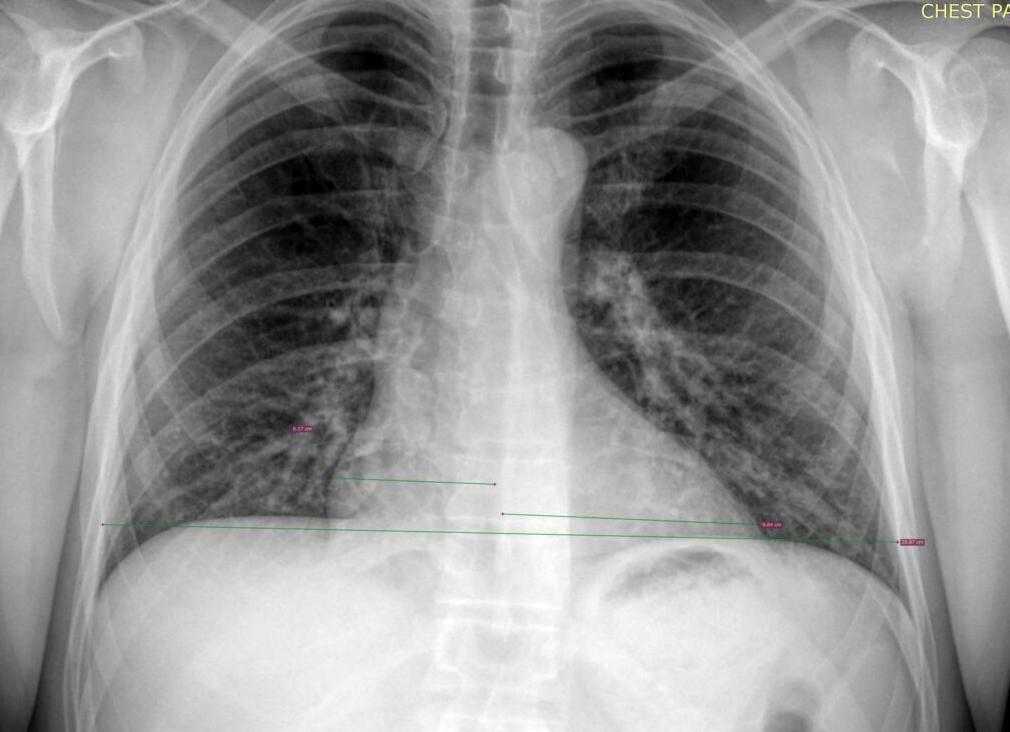

Рентгенограмма сердца помогает определить его расположение в грудной клетке, конфигурацию и размеры, а также найти изменения в аорте, легочных сосудах. Для точного выявления отклонений от нормы используют три проекции (иногда и четыре), а также заполнение пищевода барием для контрастирования границ. Метод считается доступным и относительно безопасным при использовании его не более 2 раз в год.

При рентгенологическом исследовании органов грудной клетки можно определить тень сердца, она напоминает овал, косо расположенный в левой половине. При плотном телосложении она стремится к горизонтальной линии, а у худощавых людей занимает более вертикальную позицию. Ближе к голове расположены магистральные сосуды. Между ними и овалом создаются углубления, которые образуют талию.

Мышечный слой сердца содержит плотную тень, она однородна по структуре, а очертания четкие и ровные, они имеют дугообразную форму. Каждая дуга – это отображение камеры сердца. Если ее часть становится прямой, то это является признаком патологии миокарда.

Пищевод расположен позади сердца. Если происходит увеличение какой-либо камеры, то он оттесняется по направлению к позвоночнику по дугам разного радиуса. Для диагностики изменений проводится измерение этой дуги.

Если происходит смещение по дуге малого радиуса в правой косой позиции, то это признак сужения митрального отверстия. При преобладании недостаточности клапанов пищевод отклоняется по дуге с большим радиусом. Также этот метод помогает установить правое расположение дуги аорты, аномальное ответвление от нее сосудов, расширение легочного ствола.

Рентгенография сердца с контрастированием пищевода является неинвазивным методом исследования сердца, в основе которого лежит наполнение пищевода контрастным веществом для улучшения визуализации контуров сердца (главным образом левого предсердия). Для этого пациенту предлагают выпить примерно чайную ложку бариевой взвеси – рентгенконтрастного вещества, которое на снимке четче обрисовывает границу между пищеводом и левым предсердием.

Рентгенография сердца с контрастированием пищевода – это одна из разновидностей рентгенологического исследования сердца, в основе которой лежит наполнение пищевода контрастным веществом для улучшения визуализации контуров сердца (главным образом левого предсердия). Изображение на полученной рентгенограмме – это отображение исходного пучка излучения, которое изменило свою интенсивность при прохождении анатомических структур грудной полости.

В рентгеновском излучении сердце формирует однородную тень. Это связано с тем, что образующие его структуры (миокард, клапаны, кровь, сосуды) очень близки по плотности. В тех местах, где ткани сердца граничат с легочной тканью, формируются контуры, на основании данных о величине которых формируется представление о состоянии мышечного «мотора».

Рентгенография сердца выполняется стандартно в прямой, боковой и косых проекциях. Контрастирование пищевода необходимо для лучшей визуализации задних отелов органа, так как он очень плотно к ним прилегает.

Для получения правой боковой проекции сердца, на которой лучше всего визуализируется пищевод и задние отделы сердца (главным образом левое предсердие) пациента нужно разместить таким образом, чтобы правая половина тела образовала с экраном угол в 45 градусов.